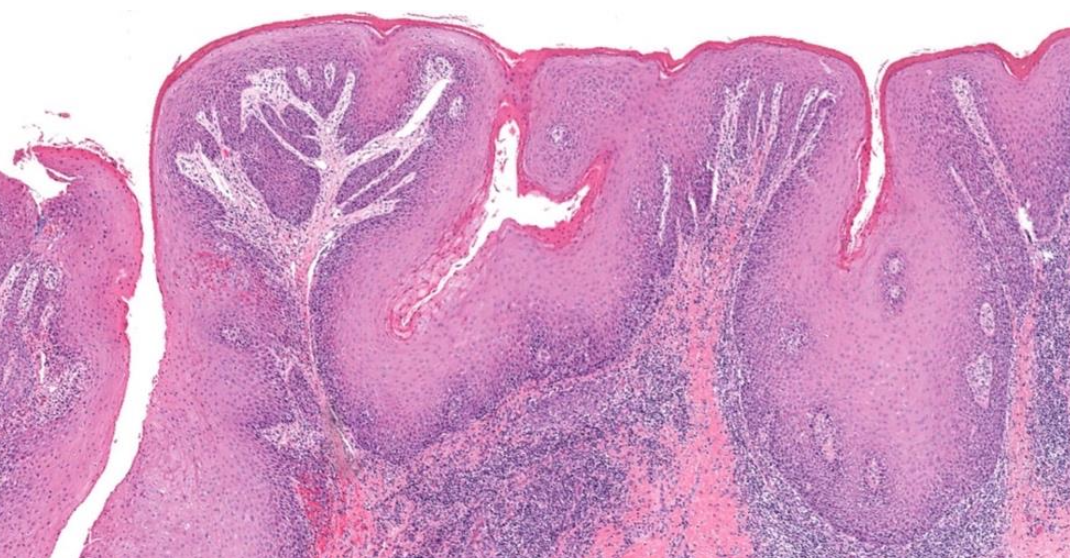

Verrucous Carcinoma(VC)

- Ackerman’s tumor

- 分化良好,不會鑽,用推的(Pushing) → 侵犯稍差

- HPV 低相關

- 四周可能有 SCC(20%)

組織

- 中央凹陷處的邊緣會有銳角

- 坑洞內充滿角蛋白

- 不會延伸超過病灶的汗腺

- 分化成熟,但角化不良,可能 keratin pearls

- 與 SCC 很難區分 → 切